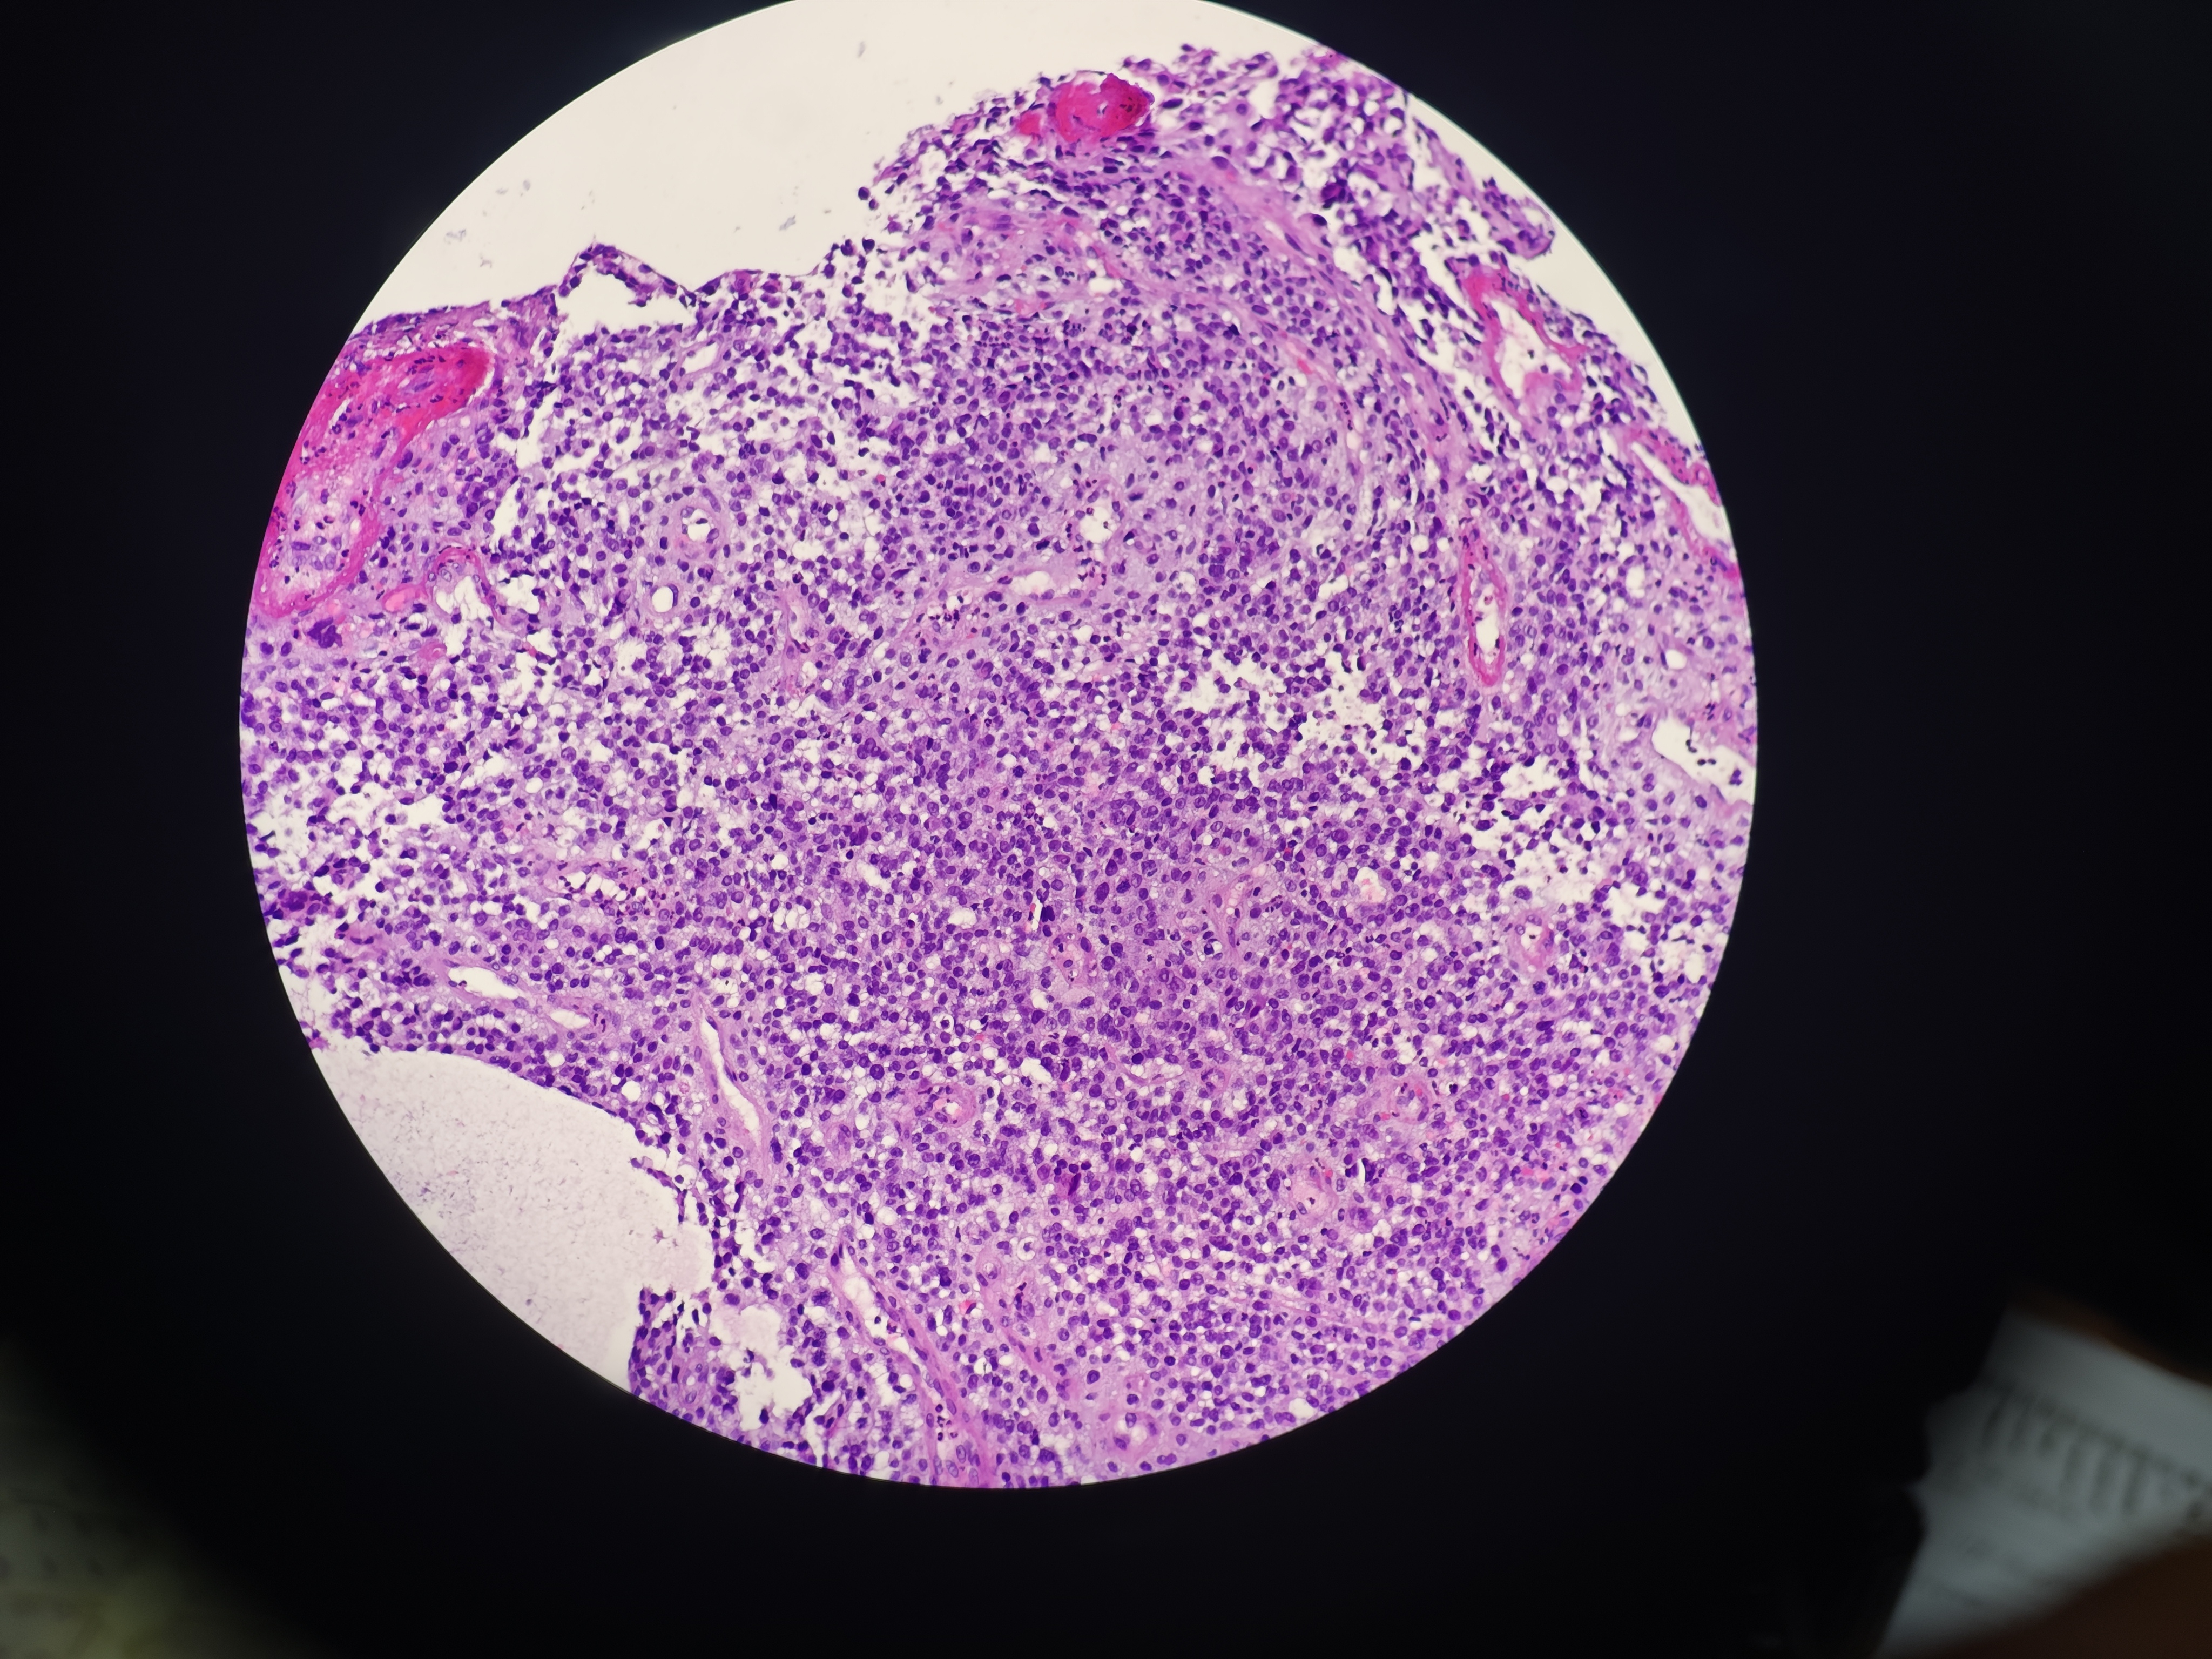

食管癌

食管距门齿33~38cm处可见环管腔半周隆起性病变,表面破溃,易出血,活检6块,质脆

食管活检

灰白软组织6块,直径0.1~0.2cm

请教老师,这个报什么癌?

图1